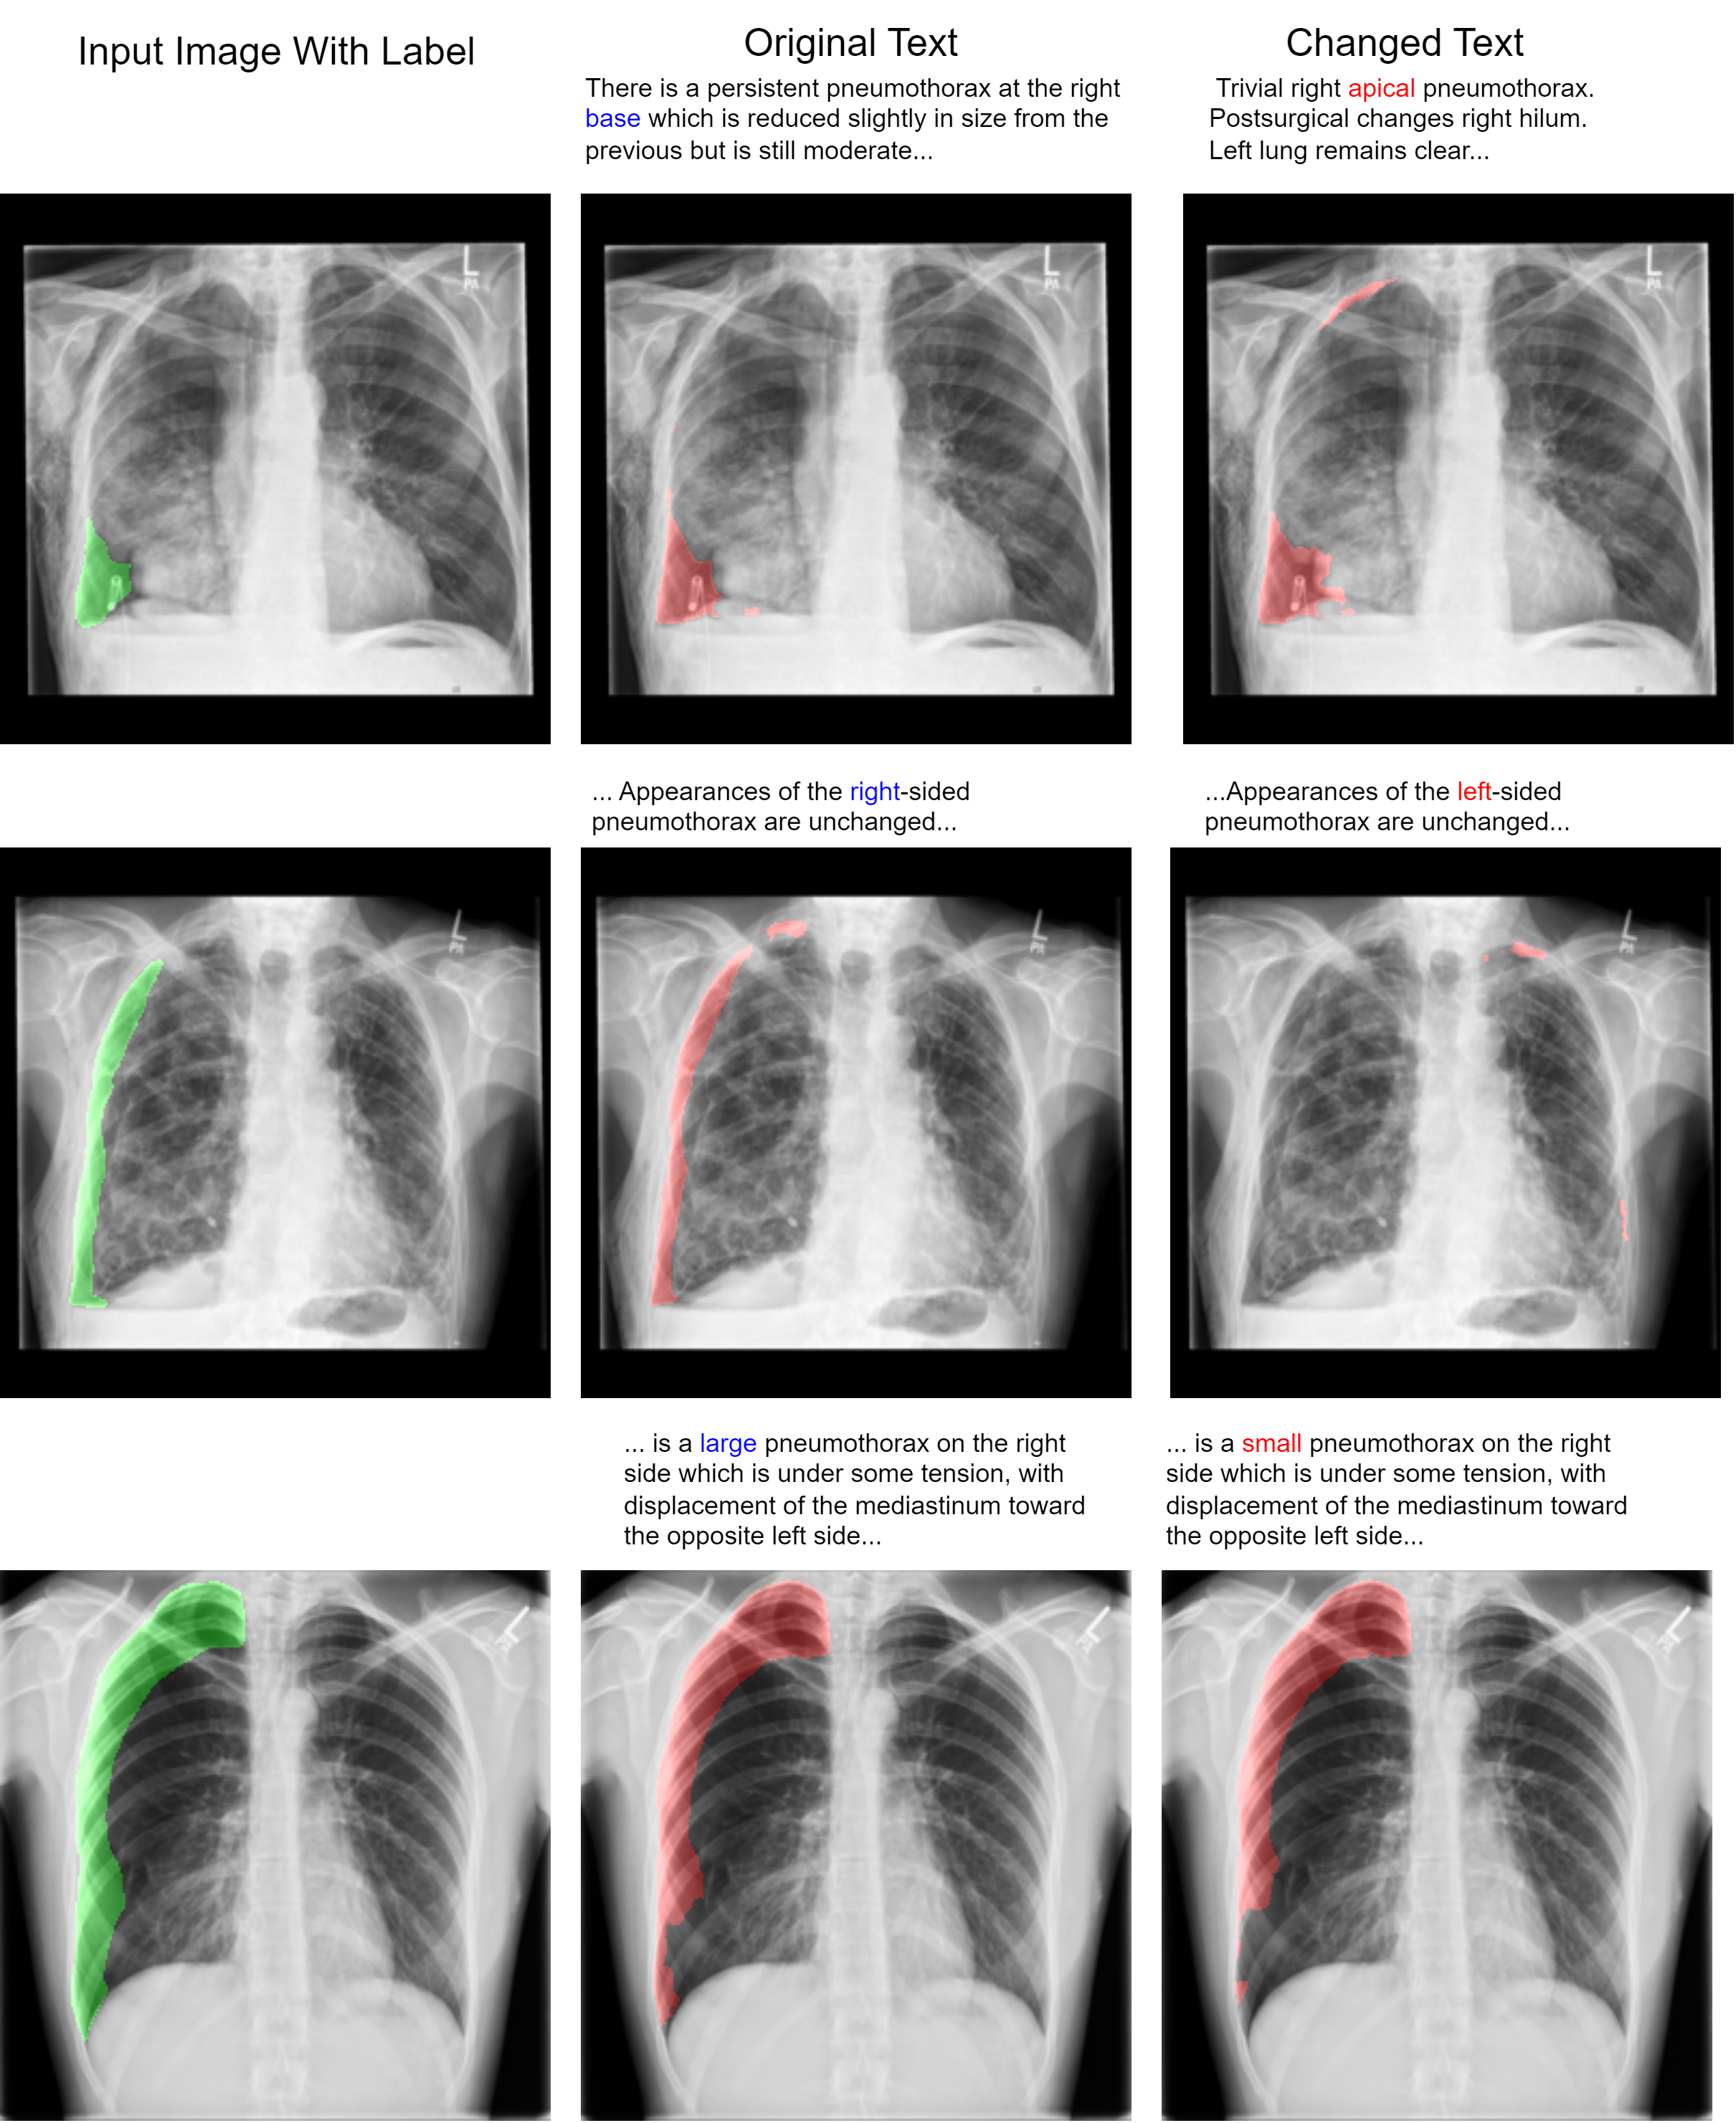

We showed the feasibility of using language from radiology reports to guide the output of segmentation algorithms. To illustrate how text can guide pixel-level predictions, we can change the input text and observe how the segmentation model reacts. For example, in Fig. 4, we changed the word “right" to “left", “large pneumothorax" to “small pneumothorax", and the location descriptor from “base" to “apical", and observed corresponding changes in the output segmentation map. We also showed that flipping an image during data augmentation can negatively impact model performance. In Fig. 5, we show that changing the text from “left" pneumothorax to “right" pneumothorax alters the attention maps from the cross-attention module, resulting in changes in the corresponding feature maps and model output.